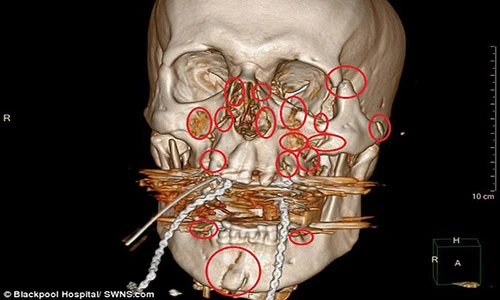

Andy không soi gương nên cũng không biết khuôn mặt mình đã kinh khủng như thế nào. Chỉ đến khi được xuất viện về nhà, anh mới được tận mắt xem tấm phim chụp X-quang hộp sọ, một mạng lưới dày đặc các mảnh kim loại và đinh vít mà bác sĩ đã dùng để có thể “sửa chữa” lại khuôn mặt của anh.

Dù phải mang trên mặt 13 mảnh kim loại và 52 đinh vít nhưng dấu hiệu đáng chú ý duy nhất anh cảm thấy sau khi trải qua cuộc đại phẫu mặt là âm thanh “tích” phát ra mỗi khi anh mở miệng. Tấm phim chụp khuỷu tay được cố định bằng đinh vít, nẹp kim loại và dây thép.